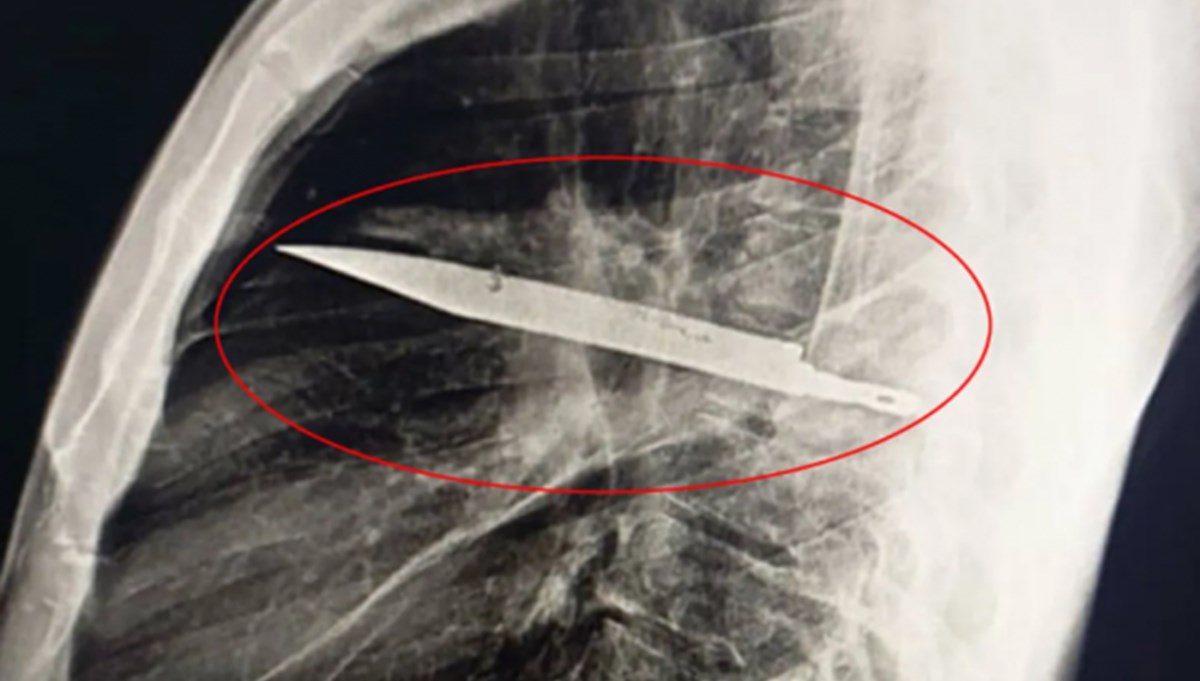

Tanzanya’da bir adam, göğüs ağrısı ve irin gelmesi şikayetiyle hastaneye başvurduğunda, tam sekiz yıldır göğsünde büyük bir bıçak parçasıyla yaşadığı ortaya çıktı. 44 yaşındaki hasta, sağ memesinden 10 gündür beyaz irin geldiğini belirterek Muhimbili Ulusal Hastanesi’ne başvurdu. Çekilen röntgende, göğsünün içinde büyük bir bıçak tespit edildi.

Adam, sekiz yıl önce kavga sırasında yüzünden, sırtından ve göğsünden yaralandığını, o dönemde hastanede sadece dikiş atıldığını hatırladığını söyledi. Ancak o dönemde bulunduğu hastanede görüntüleme imkanı olmadığı için vücudunda yabancı cisim fark edilmedi. Daha da şaşırtıcı olan, bıçağın yıllar boyunca hiçbir ağrı ya da rahatsızlık vermemiş olmasıydı. Doktorlar, bıçağın sağ kürek kemiğinden girip hayati organlara zarar vermeden göğüste kaldığını, irin oluşumunun ise çevresinde biriken ölü dokudan kaynaklandığını açıkladı. Bıçak başarılı bir operasyonla çıkarıldı, ölü doku temizlendi. 24 saat yoğun bakımda kalan hasta, 10 gün boyunca tedavi gördükten sonra taburcu edildi.